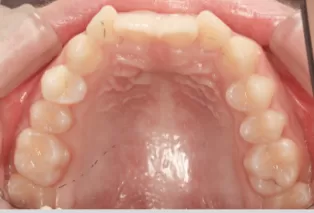

Intraoral photos